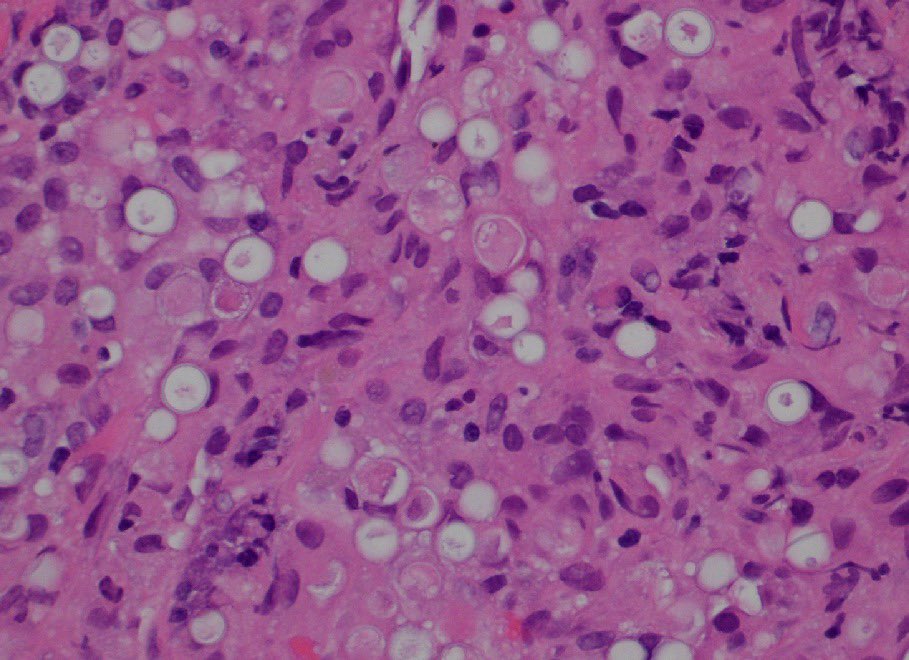

"BOW TIE". Papillary thyroid carcinoma. #FNA Thyroid. #Entpath #endopath #pathology #pathtwitter #PathTweetAward @MSWPathology @MyCytopathology @SamKhader